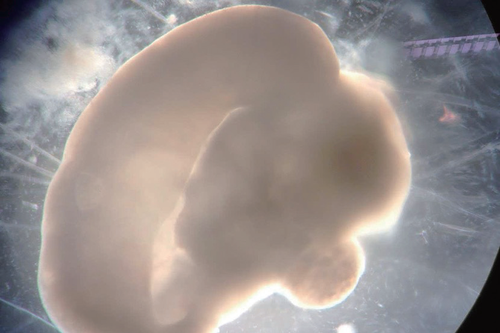

百日脑类器官